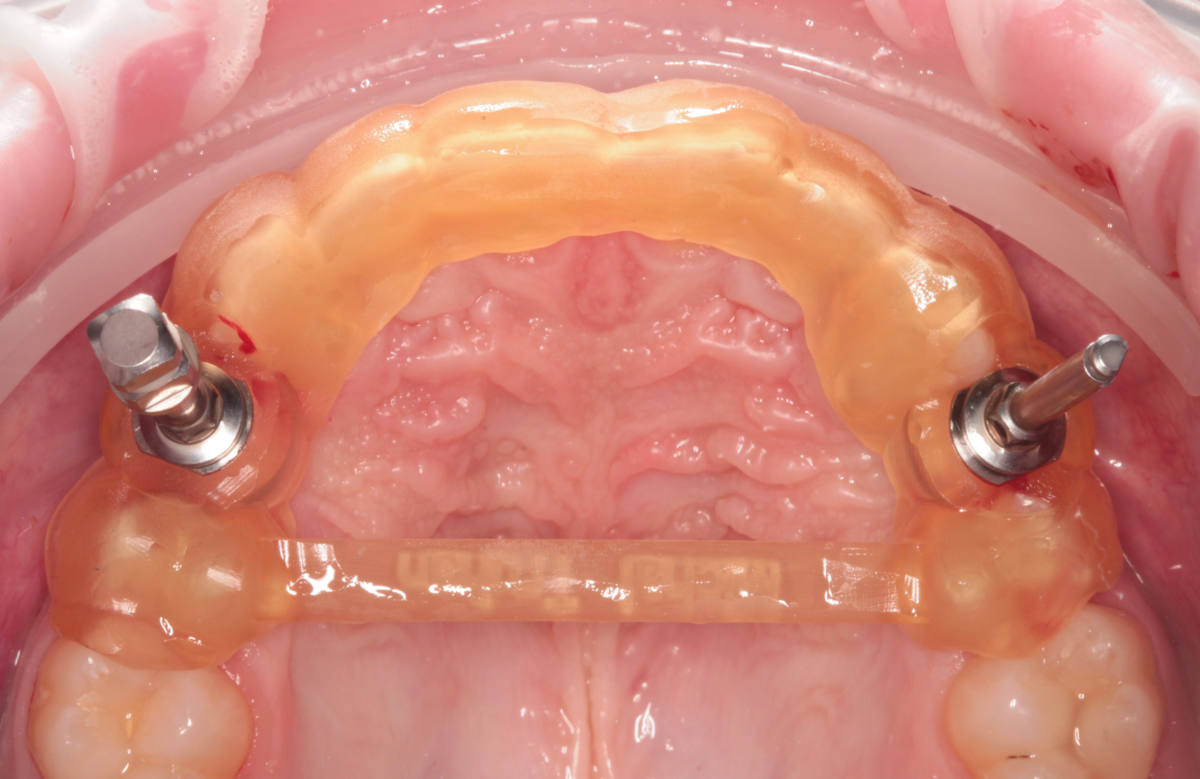

Navigovaná chirurgia, 3 implantátov

Autor práce Dr. Michal Repaši

Zubný technik Vasil Csopej